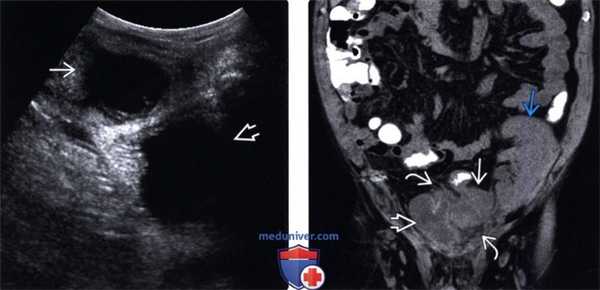

(Левый) У пациента после трансплантации почки на продольном УЗ срезе по средней линии таза определяется дивертикулярный абсцесс. Жировая клетчатка между абсцессом и мочевым пузырем воспалена.

(Правый) У этого же пациента при КТ без контрастного усиления на корональной томограмме визуализируется абсцесс, локализующийся между трансплантатом почки и мочевым пузырем. При КТ без контрастного усиления гораздо лучше визуализируется исчерченность воспаленной жировой клетчатки.

4. УЗИ внутрибрюшного абсцесса:

• Неоднородное скопление жидкости с включениями невысокой эхогенности, с наличием перегородок, септ, или многокамерное: о Эхогенные включения отражают наличие дебриса в абсцессе:

- Усложнение структуры абсцесса предполагает наличие более густого, вязкого содержимого

- Комплексная структура абсцесса при УЗИ предполагает затруднения при его дренировании (особенно при помощи тонкого катетера)

о Эффект дорсального усиления в значительной степени зависит от состава жидкости в структуре абсцесса:

- Абсцессы, содержащие вязкую, густую, белковую жидкость дают относительно небольшой эффект дорсального усиления

о Центр абсцесса лишен сосудов при цветовой допплерографии, с усилением кровотока по периферии о Жир вокруг абсцесса может выглядеть крайне эхогенным из-за воспаления:

- При цветовой допплерографии определяется усиление кровотока в воспаленной жировой ткани

- Внутренние эхогенные очаги с артефактами вследствие реверберации и «грязной» (размытой) акустической тенью позволяют предположить наличие газа